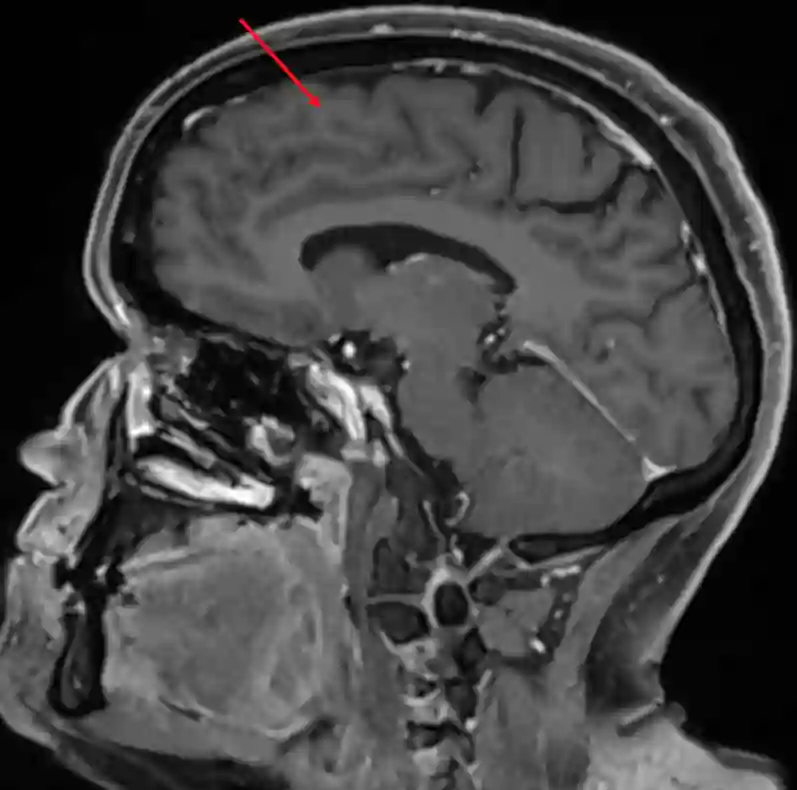

Gyrus frontalis superior im sagittalen MRI.

Gyrus frontalis superior im sagittalen MRI (T1 Sequenz mit Kontrastmittel).